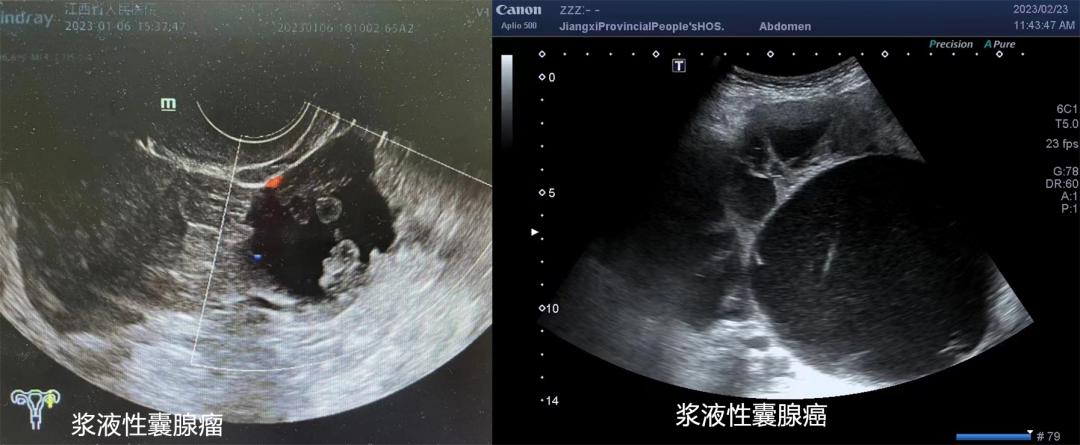

超声提示囊肿为囊实性或内壁有乳头样突起时,恶性风险增至10%。

超声检查可以初步判定囊肿为“良性”、 “恶性可能性”或“不确定性”,据此,可协助医生选择进一步的检查及手术干预。

3)超声显示囊肿最大直径≥10cm、内含乳头或实性成分、形态不规则、合并腹水、彩色多普勒超声提示囊肿血流丰富,均应进一步除外恶性肿瘤的可能。